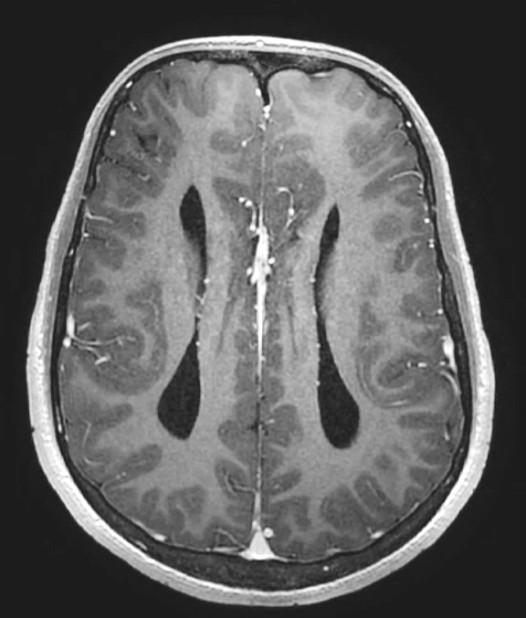

Parallel ventricles

Colpocephaly

Longhorn or Viking helmit frontal horns

High riding 3rd vent